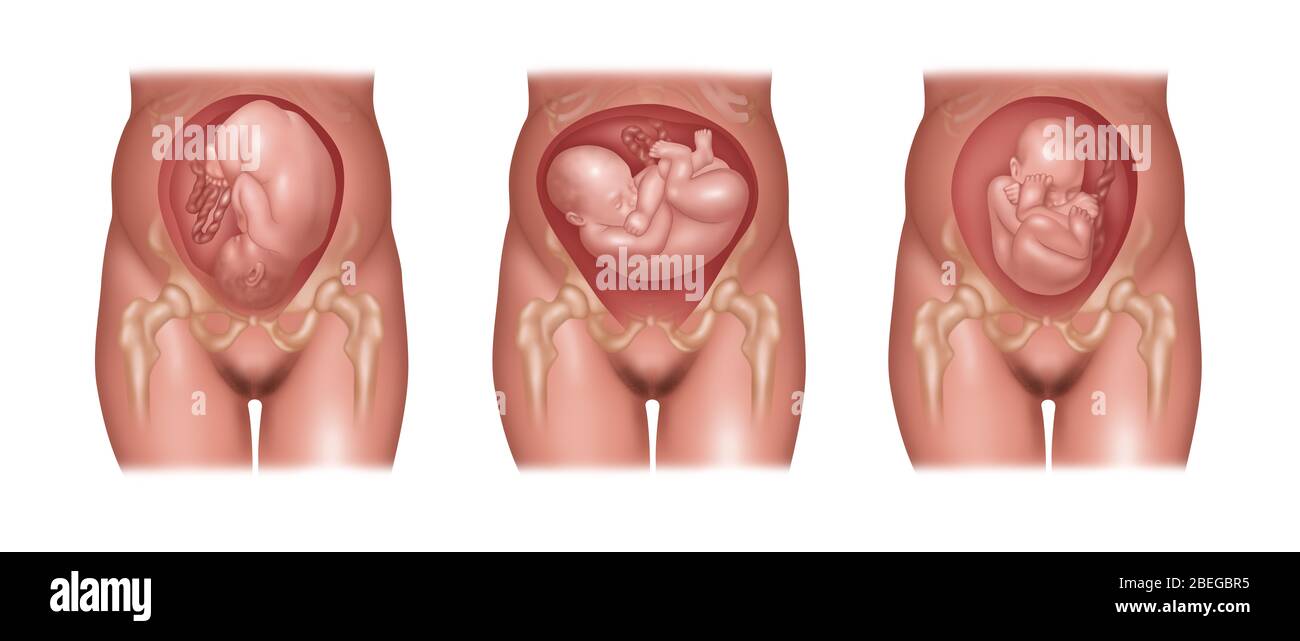

Fetus Positions in Uterus, Illustration Stock Photohttps://www.alamy.com/image-license-details/?v=1https://www.alamy.com/fetus-positions-in-uterus-illustration-image353173031.html

Fetus Positions in Uterus, Illustration Stock Photohttps://www.alamy.com/image-license-details/?v=1https://www.alamy.com/fetus-positions-in-uterus-illustration-image353173031.htmlRF2BEGBPF–Fetus Positions in Uterus, Illustration

Fetus Positions in Uterus, Illustration Stock Photohttps://www.alamy.com/image-license-details/?v=1https://www.alamy.com/fetus-positions-in-uterus-illustration-image353173074.html

Fetus Positions in Uterus, Illustration Stock Photohttps://www.alamy.com/image-license-details/?v=1https://www.alamy.com/fetus-positions-in-uterus-illustration-image353173074.htmlRF2BEGBT2–Fetus Positions in Uterus, Illustration

Fetus Positions in Uterus, Illustration Stock Photohttps://www.alamy.com/image-license-details/?v=1https://www.alamy.com/fetus-positions-in-uterus-illustration-image353173049.html

Fetus Positions in Uterus, Illustration Stock Photohttps://www.alamy.com/image-license-details/?v=1https://www.alamy.com/fetus-positions-in-uterus-illustration-image353173049.htmlRF2BEGBR5–Fetus Positions in Uterus, Illustration

Fetus Positions in Uterus, Illustration Stock Photohttps://www.alamy.com/image-license-details/?v=1https://www.alamy.com/fetus-positions-in-uterus-illustration-image353173070.html

Fetus Positions in Uterus, Illustration Stock Photohttps://www.alamy.com/image-license-details/?v=1https://www.alamy.com/fetus-positions-in-uterus-illustration-image353173070.htmlRF2BEGBRX–Fetus Positions in Uterus, Illustration

Fetus Positions in Uterus, Illustration Stock Photohttps://www.alamy.com/image-license-details/?v=1https://www.alamy.com/fetus-positions-in-uterus-illustration-image353173044.html

Fetus Positions in Uterus, Illustration Stock Photohttps://www.alamy.com/image-license-details/?v=1https://www.alamy.com/fetus-positions-in-uterus-illustration-image353173044.htmlRF2BEGBR0–Fetus Positions in Uterus, Illustration